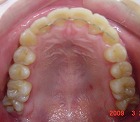

矯正後

s-090324 upper teeth cut.jpg

s-090324 lower teeth cut.jpg